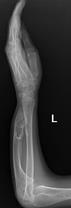

桡骨陈旧性骨折骨不连、畸形

尺骨短缩畸形并软骨瘤 桡骨小头脱位